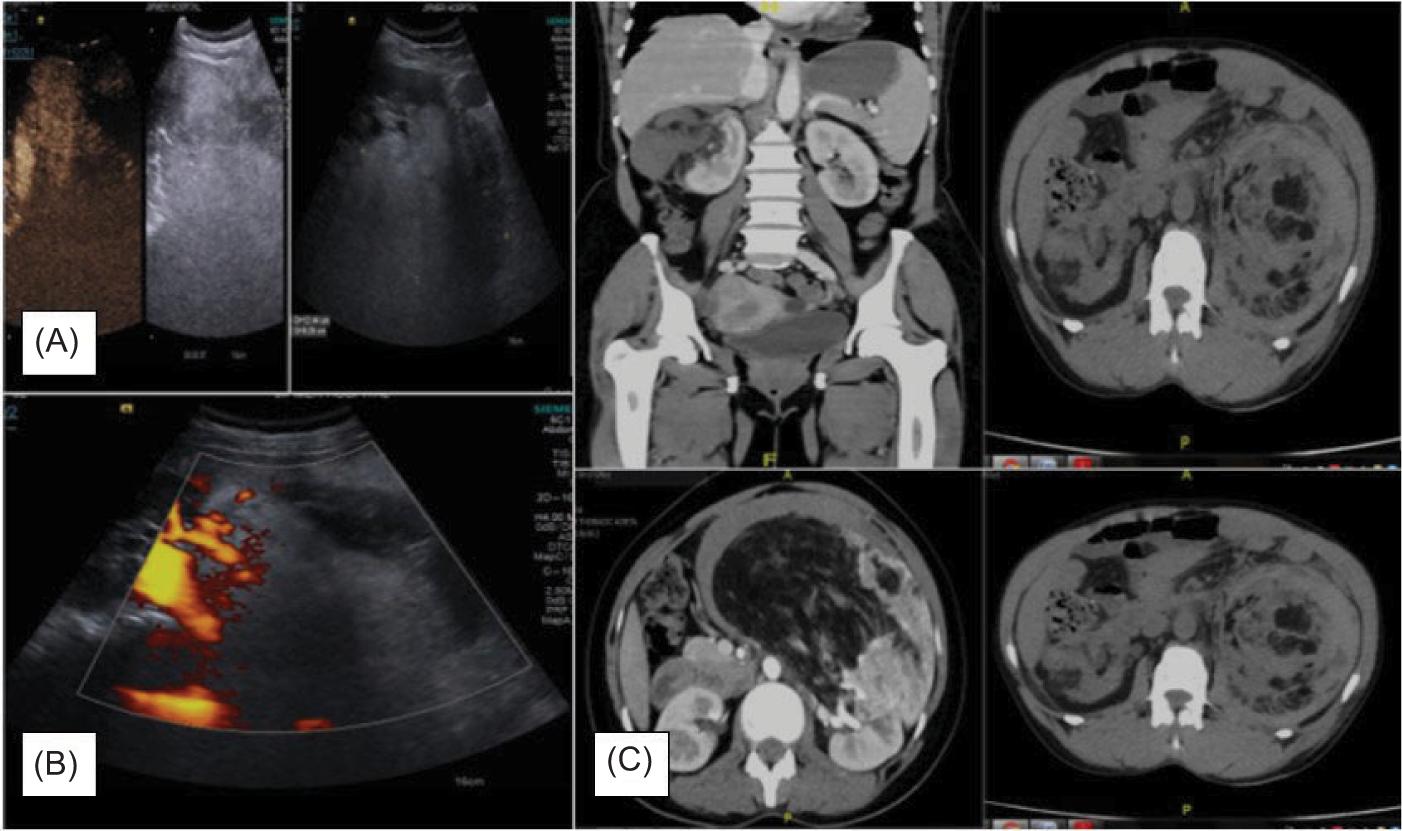

On CT scan, the size of the tumor varied at a wide range, with the smallest AML being 5.5 × 4.5 × 5 cm and the largest being 25 × 15 × 12 cm. CT scan was effective in both perinephric hematoma and AMLs in all the cases (Figure 1). Two of the patients had bilateral AML (Table 2).

Figure 1: (A) Ultrasonographic images of renal angiomyolipoma; (B) Doppler images showing perirenal haemorrhage, that is, Wunderlich syndrome; (C) Contrast-enhanced computed tomography showing renal angiomyolipoma with Wunderlich Syndrome.